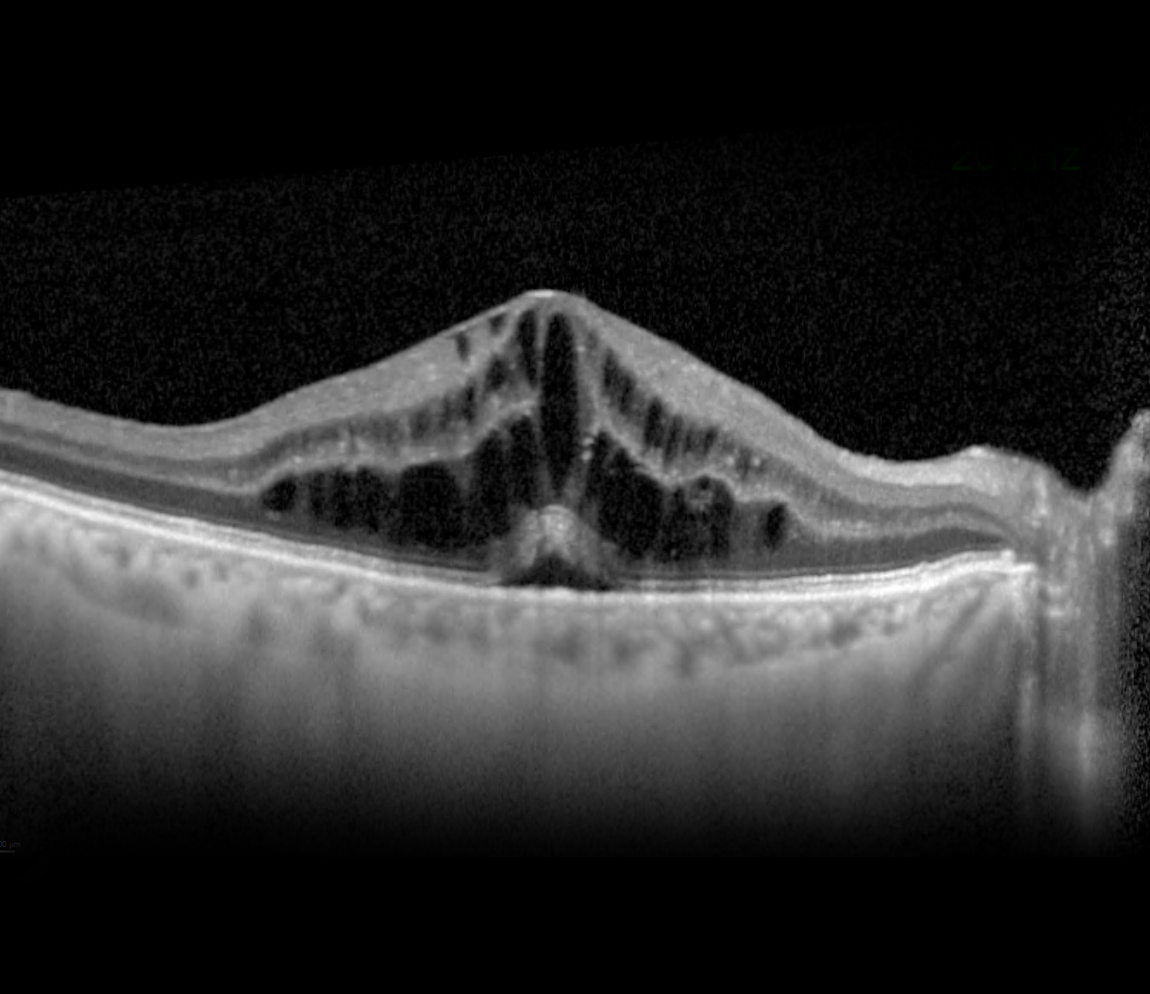

In wet AMD, the build-up of drusen and degeneration of the RPE has started to impair the supply of oxygen to the photoreceptor cells. In response, the retina releases the signaling molecule VEGF, to encourage the formation of new, blood vessels within the retina. However, such new vessels are structurally immature with fragile vessel walls that can suddenly leak fluid/blood. The fluid forms little cystoid spaces within or beneath the retina, distorting vision. Left untreated, permanent vision loss may occur.

The image illustrates changes in the macula such as cystoid changes and drusen.